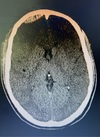

50 anos, hemiparesia esquerda. Qual Diagnóstico?

AVCi Oclusão da artéria cerebral média direita